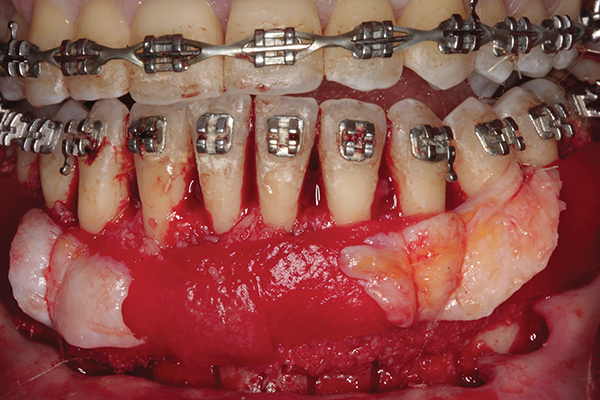

Fig 2. Full-thickness flap reflection. Note

dehiscence and fenestrations throughout. Orthodontic walls are limited to nonexistent.

Fig 3. Corticotomy cuts performed.

Figure 3